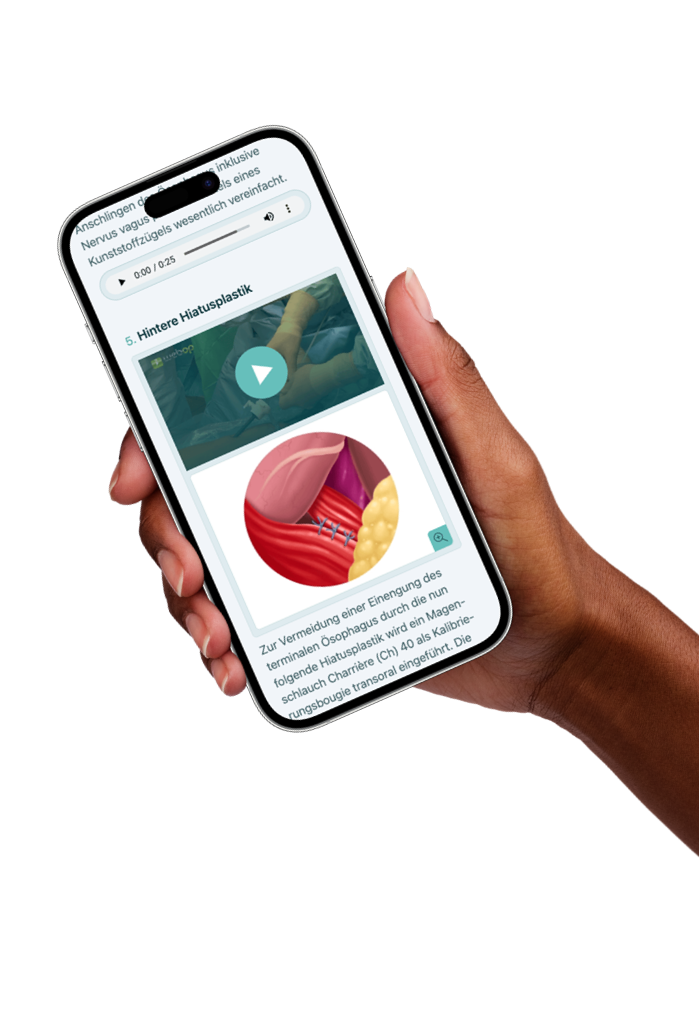

Lehrbeiträge aus den Bereichen der Allgemein- und Viszeralchirurgie, Gefässchirurgie, Gynäkologie, Thoraxchirurgie, Robotik und Handchirurgie Schritt für Schritt in Videos erklärt.

Von Chirurg:innen – für Chirurg:innen

E-Learning Plattform

für Chirurgie